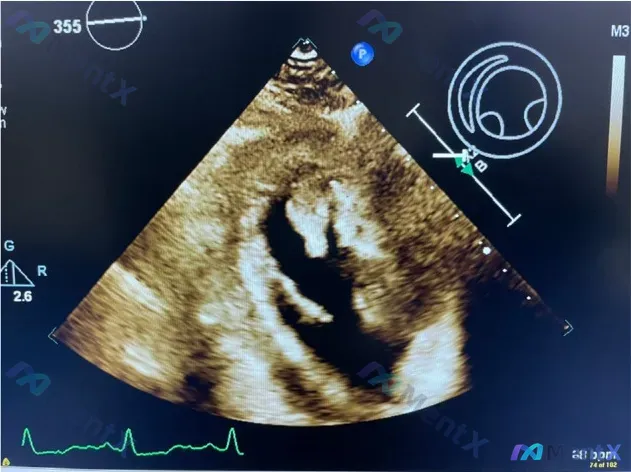

看到一份很有警示意义的病例资料,整理了一下思路和大家分享: --- 病例核心信息 - 关键阳性发现:经胸超声心动图明确提示 左心室大量心尖部血栓 - 提供的静态影像:胸骨旁主动脉瓣短轴切面 - 可见主动脉瓣叶回声略增强,提示可能存在瓣叶增厚/钙化 - 该切面内未见明显占位 - 室间隔结构连续,未见明...